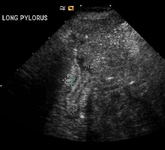

Pyloric stenosis

Pyloric ultrasound. <1> interval: length; <2> interval: muscle width

From the collection of Dr Jeffrey S. Upperman; used with permission